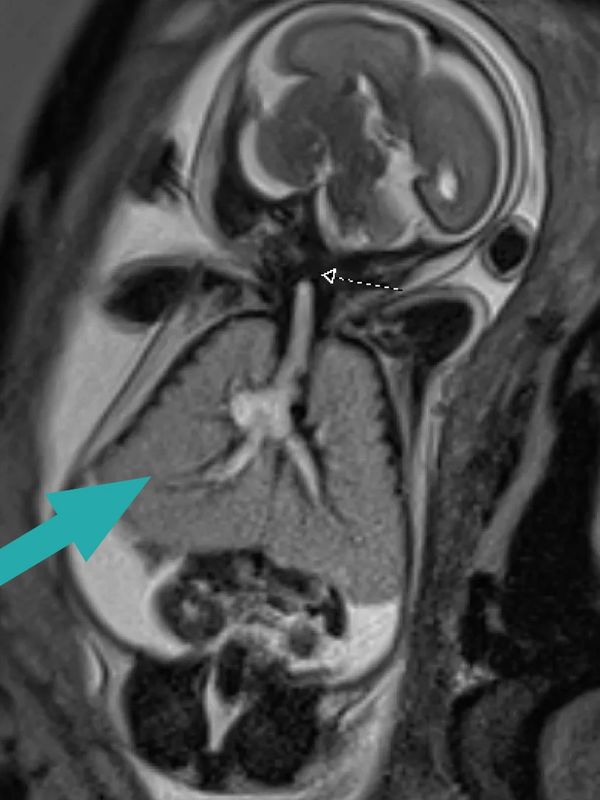

(pic: fetal MRI or a child with CHAOS, the small arrow depicts the area of laryngeal atresia. The large arrow shows the overexpanded lungs)